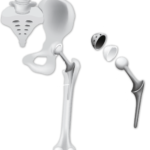

بخشی از نمونه کارها

نمونه کارهای قبل و بعد